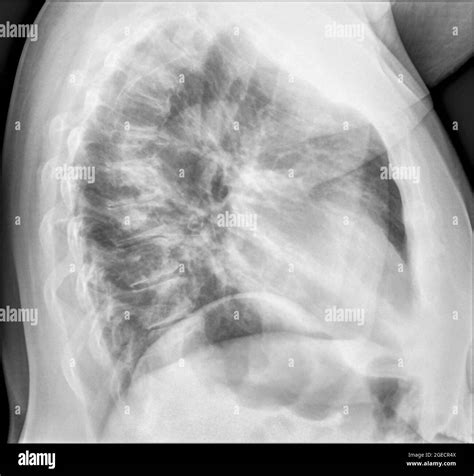

Lateral Chest X Ray

A Lateral Chest X Ray is a radiographic image taken from the side of the body, providing a different perspective compared to the standard anteroposterior (AP) or posteroanterior (PA) views. This lateral view is particularly useful for assessing the depth and position of structures within the chest, such as the heart, lungs, and diaphragm.

Interpreting a Lateral Chest X Ray requires a trained eye and knowledge of normal anatomy. Key structures to assess include:

• The heart and its borders

• The lungs and any visible abnormalities

• The diaphragm and its position

• The ribs and spine

Abnormalities that may be detected on a lateral chest X-ray include:

• Pneumonia, which may appear as areas of increased opacity in the lungs

• Pleural effusions, which show up as fluid collections around the lungs

• Pneumothorax, characterized by the presence of air in the pleural space

• Lung masses or nodules, which can indicate tumors or other growths